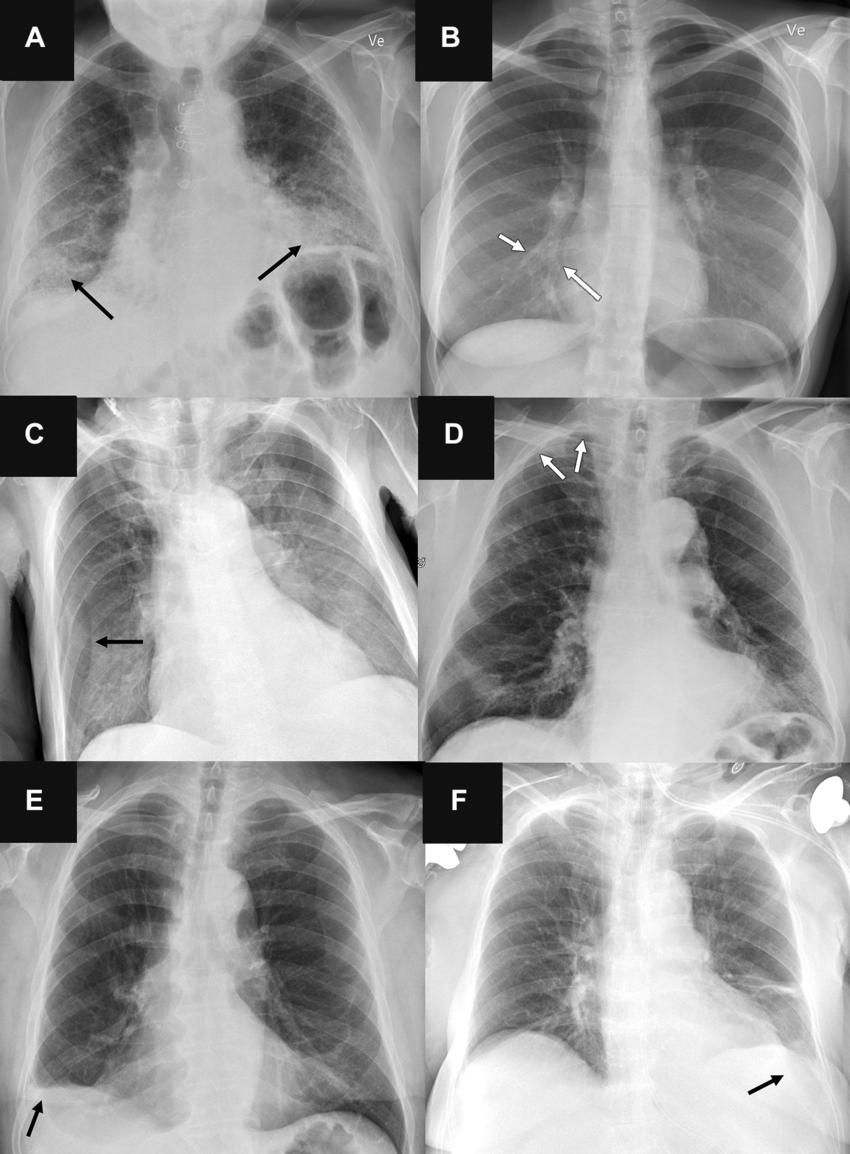

Figure 6. Representative chest radiographs in six patients show (A, C, E) false-positive findings and (B, D, F) false-negative findings as identified by the artificial intelligence (AI) tools. These examples were all correctly classified by the clinical radiology reports. (A) Posteroanterior chest radiograph in a 71-year-old male patient who underwent examination due to progression of dyspnea shows bilateral fibrosis (arrows), which was misclassified as airspace disease by all four AI tools. (B) Posteroanterior chest radiograph in a 31-year-old female patient referred for radiography due to month-long coughing shows subtle airspace opacity at the right cardiac border (arrows), which was missed by all AI tools. (C) Anteroposterior chest radiograph in a 78-year-old male patient referred after placement of a central venous catheter shows a skin fold on the right side (arrow), which was misclassified as pneumothorax by all AI tools. (D) Posteroanterior chest radiograph in a 78-year-old male patient referred to rule out pneumothorax shows very subtle apical right-sided pneumothorax (arrows), which was missed by all AI tools except for vendor B (with the high sensitivity threshold). (E) Posteroanterior chest radiograph in a 72-year-old male patient referred for radiography without a specified reason shows chronic rounding of the costophrenic angle (arrow), which was mistaken for pleural effusion by all AI tools and verified according to the reference standard in a corresponding chest CT image. (F) Anteroposterior chest radiograph in a 76-year-old female patient referred for radiography due to suspicion of congestion and/or pneumonia shows a very subtle left-sided pleural effusion (arrow), which was missed by all three AI tools that were capable of analyzing anteroposterior chest radiographs for pleural effusion.